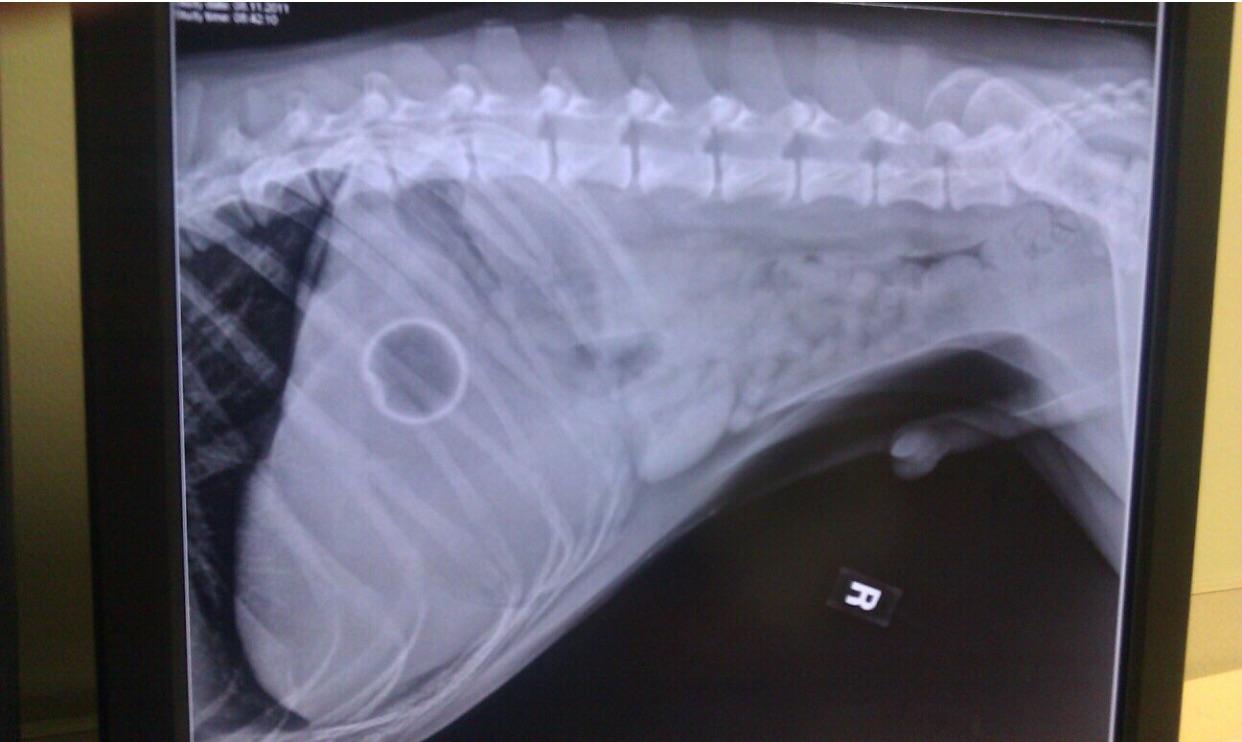

Dog Swallowed A Thumb Tack . If it is still in their mouth, carefully remove it using tweezers. Some common signs include difficulty swallowing, drooling excessively,. Common symptoms of a string obstruction include vomiting, diarrhea, loss of appetite, abdominal pain, and lethargy. First, prevent your dog and other opportunistic pets from eating more toothpicks. If the staple has been swallowed,. One thing new research makes clear. This involves removing them from the area and clearing up any spills. If your dog ate a toothpick, you should call your veterinarian for advice immediately. If your dog has swallowed a toothpick, it is important to take immediate action. In some cases, dogs may. First, try to determine if the dog swallowed the staple or if it is still stuck in their mouth. If your dog has swallowed something sharp, such as a bone fragment or needle, do not attempt to induce vomiting. Keep reading to know what our vets recommend to do in this situation. The signs that your dog may have swallowed a thumbtack can vary. My dog swallowed a toothpick.

Puppy who swallowed thumb tack saved by AES vets who used 2.50 Dog Swallowed A Thumb Tack If the staple has been swallowed,. First, prevent your dog and other opportunistic pets from eating more toothpicks. This involves removing them from the area and clearing up any spills. If it is still in their mouth, carefully remove it using tweezers. Common symptoms of a string obstruction include vomiting, diarrhea, loss of appetite, abdominal pain, and lethargy. Keep reading. Dog Swallowed A Thumb Tack.

Puppy who swallowed thumb tack saved by AES vets who used 2.50 Dog Swallowed A Thumb Tack This involves removing them from the area and clearing up any spills. Keep reading to know what our vets recommend to do in this situation. The signs that your dog may have swallowed a thumbtack can vary. If your dog has swallowed a toothpick, it is important to take immediate action. First, prevent your dog and other opportunistic pets from. Dog Swallowed A Thumb Tack.

Puppy who swallowed thumb tack saved by AES vets who used 2.50 Dog Swallowed A Thumb Tack First, try to determine if the dog swallowed the staple or if it is still stuck in their mouth. This involves removing them from the area and clearing up any spills. In some cases, dogs may. Common symptoms of a string obstruction include vomiting, diarrhea, loss of appetite, abdominal pain, and lethargy. If it is still in their mouth, carefully. Dog Swallowed A Thumb Tack.